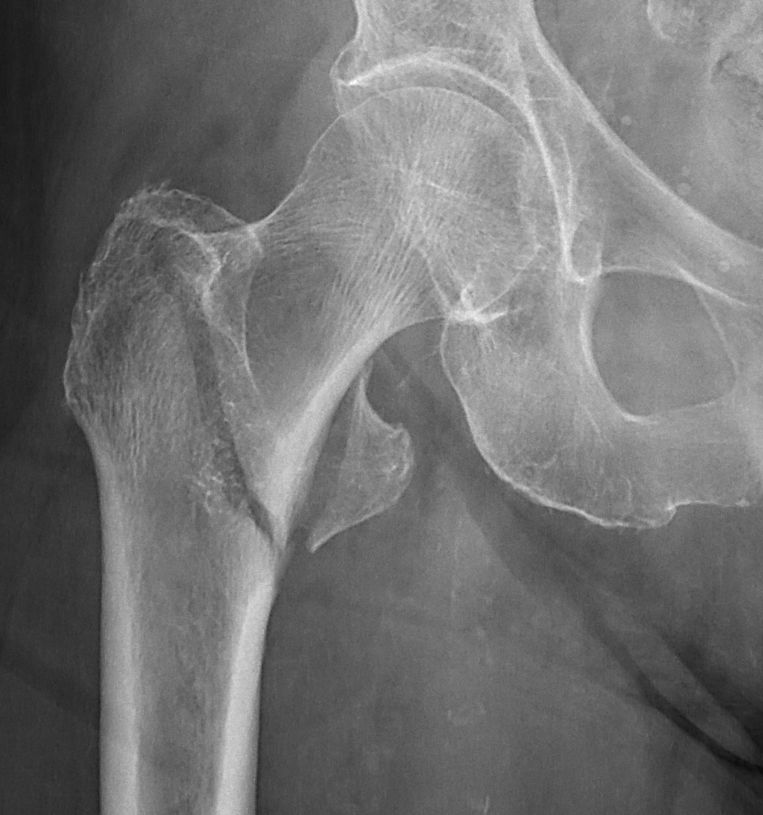

- Cervikal, fraktur av kollum femoris. Klassificeras enligt Garden som bedöms på frontalbild. Det finns något olika tolkningar av denna klassifikation. Ofta används istället "Garden 1-2" för odislocerad eller måttligt dislocerad fraktur och "Garden 3-4" för mer dislocerad.

- Garden 1: inkomplett fraktur med intakt inferior kant, kan vara valgusställd [1]

- Garden 2: genomgående fraktur utan annan felställning än kompression [1]

- Garden 3: genomgående fraktur med kontakt inferiort, varusställd [1]

- Garden 4: genomgående fraktur, parallellförskjuten, kaput ligger rätt i acetabulum [1]